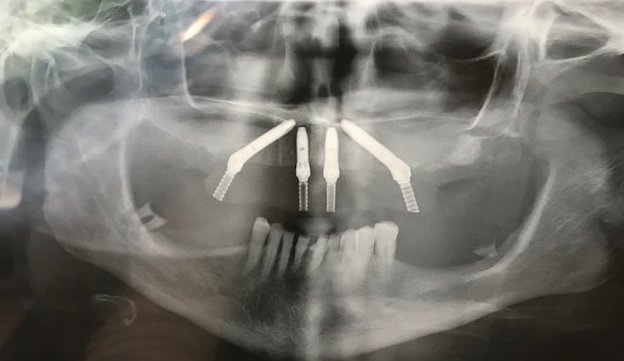

Gli impianti osteointegrati di titanio che utiliziamo sono tutte prime marche, dipendendo da ogni singolo caso e dal tipo di osso: Nobel Biocare, MIS Iberica, BTI e Straumann.